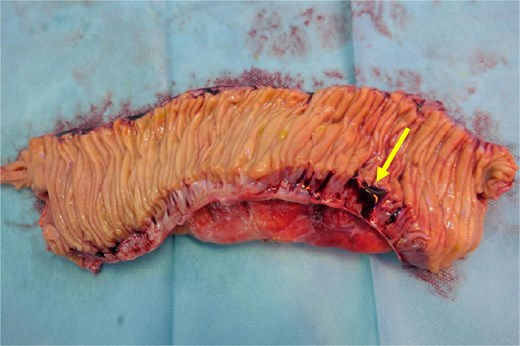

A computed tomography angiography (CTA) of the abdomen was performed, it showed a long segment of the small bowel with wall thickening in the right lower quadrant, accompanied by a inflammatory change in the mesenteric fat with multiple air bubbles, and free fluid in the pelvis, suggestive of hollow organ perforation (Fig. 1). Given the high suspicion of hollow organ perforation and clinical signs of peritonitis, an indication for exploratory laparotomy was established and performed as an emergency procedure. An antibiotic therapy with piperacillin/tazobactam was empirically initiated preoperatively.

CTA showing a long segment of small bowel with inflammatory wall thickening and fat stranding of the mesentery with multiple air bubbles.